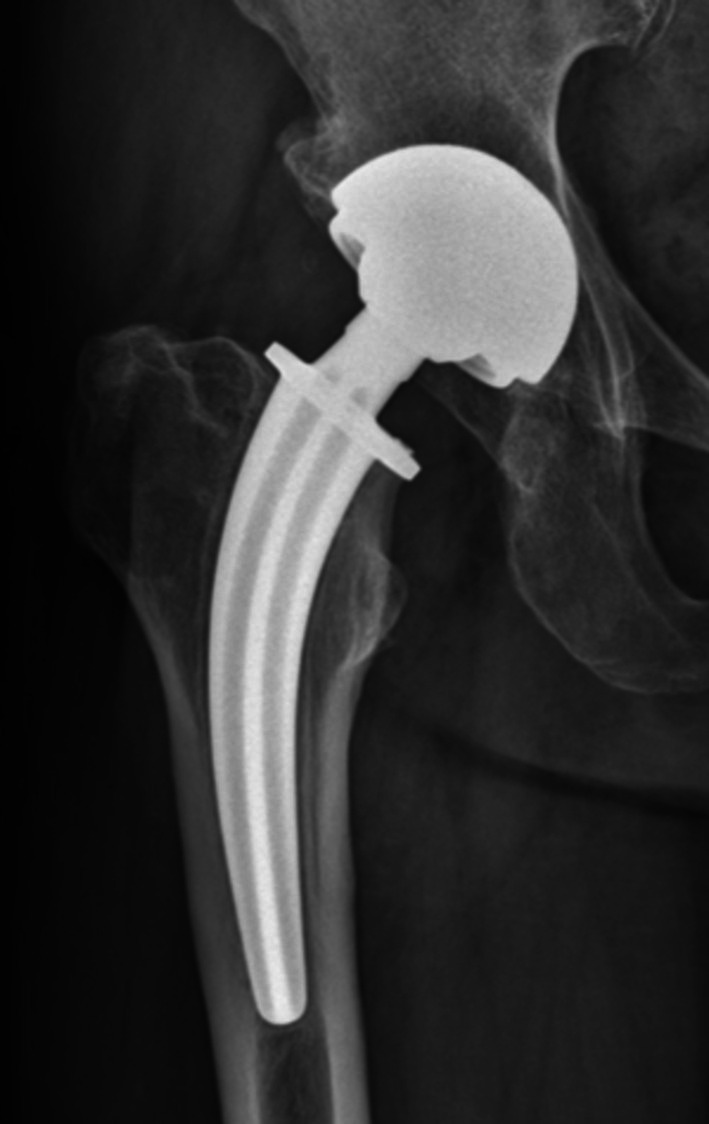

Objective: The Collum Femoris Preserving (CFP) stem offers biomechanical advantages in total hip arthroplasty (THA). However, aseptic loosening remains the most common cause of failure and other severe complications, with specific risk factors associated with the CFP stem remaining inadequately defined. This study aims to investigate the possible factors associated with aseptic loosening.

Methods: This study retrospectively analyzed patients who underwent primary THA with the CFP stem from January 2004 to December 2009 in our institution. Patients were divided into two groups based on whether there was aseptic loosening. Demographic and imaging parameters were collected from medical records and the hospital's Picture Archiving and Communication System (PACS). Comparative analyses were conducted, and variables with significant differences were subjected to Cox regression to identify independent risk factors of aseptic loosening.

Results: A total of 469 hips were included, with 52 hips (11.1%) of aseptic loosening identified. Seven independent risk (protective) factors were found, including ceramic-on-polyethylene (COP) bearing surfaces (Hazard Ratio = 2.084, 95% Confidence Interval: 1.043-4.166, p = 0.038), history of steroid therapy (HR = 2.393, 95% CI: 1.056-5.425, p = 0.037), neck resorption ratio (NRR) (HR = 1.019, 95% CI: 1.005-1.033, p = 0.008), bone mineral density (BMD) (HR = 0.933, 95% CI: 0.891-0.976, p = 0.003), canal fill ratio (CFR) (HR = 0.951, 95% CI: 0.923-0.980, p = 0.001), cortical index (HR = 0.933, 95% CI: 0.891-0.976, p = 0.003), and varus/valgus angle between 3° and 6° (HR = 4.427, 95% CI: 2.303-8.509, p < 0.001), varus/valgus angles > 6° (HR = 8.854, 95% CI: 3.704-21.165, p < 0.001).

Conclusion: This study identifies key risk factors contributing to aseptic loosening, including COP bearing surfaces, steroid therapy history, excessive femoral neck resorption, and significant varus/valgus malalignment. Conversely, higher BMD, improved cortical index, and favorable CFR were protective against loosening. These findings underscore the need for careful preoperative assessment and precise intraoperative positioning to optimize long-term implant stability.